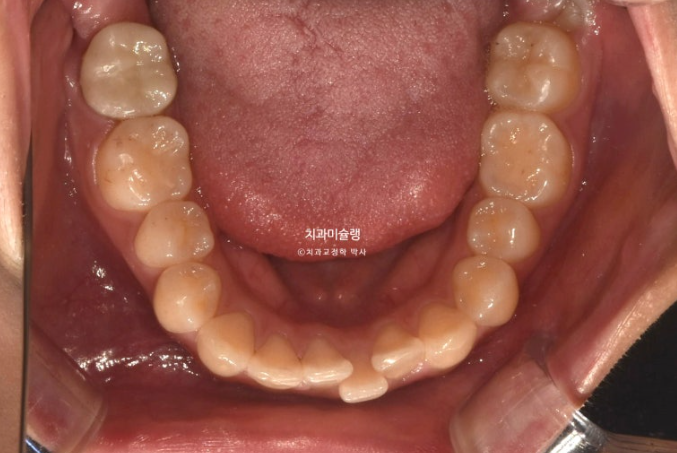

24년 여름방학을 이용해서 교정상담을 온 유학생 환자분입니다.

측절치의 개방교합, 아래 앞니 덧니 등 보입니다.

우측 교합관계는 1급에 가깝지만

좌측 교합관계는 2급입니다.

위 아래 치아들이 일대일로 물리면 2급 또는 3급 교합관계 입니다.

송곳니에서 큰어금니까지 절반씩 엇갈려 물리는 교합이 1급 교합입니다.